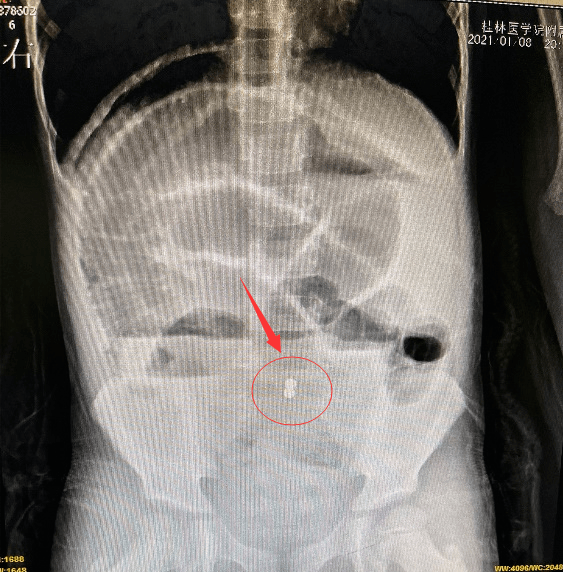

桂林4岁男童误食糖果致肠穿孔可能你家也有

图片尺寸563x572